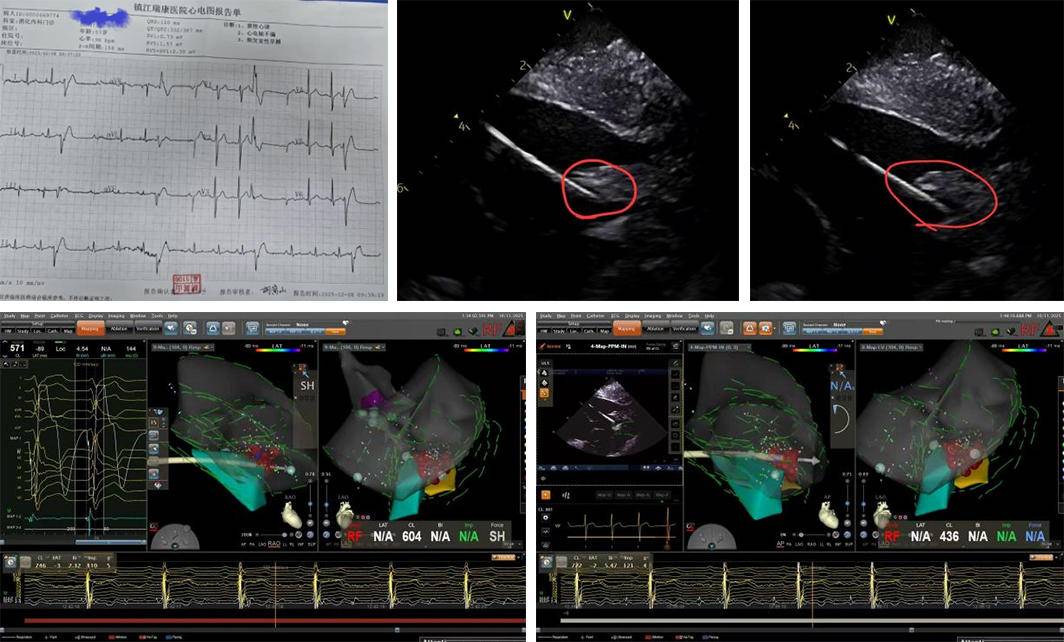

胸心外科主任陈晓军于2025年7月前往浙江大学医学院附属邵逸夫医院心外科,跟随国内著名心脏外科专家钱希明教授团队进行 为期半个月的深入学习。学成归来后,陈晓军主任带回国际先进的心脏外科管理理念,并引进前沿技术。 2025/08/13 wisonic 68 圣 [ 结束检查 P7-3T-H(D) TEE Labat SE AP100 MI0.4 TIB0.20 9:42:06 Pat T 37°C TEE T 40.8°C = 术前 180 0 53 10 12 齐鲁晚报.齐鲁壹点王文彬通讯员刘超杜晓萍 wisome LVLJ/VO/ 1. [ـ] 结束检查 P7-3T-H(D) TEE 10:52:33 AP100 MI0.4 TIB0.26 Labat SE Pat T 37°C 3 TEE T 41.7℃ 180 0 术中 5. . S 10 8月13日,滨州市中心医院胸心外科独立完成医院首例改良食道超声(TEE)引导下卵圆孔(PFO)介入封堵术。该手术的成功开展, 标志着医院心脏外科在结构性心脏病微创介入治疗领域取得重大突破,实现了该技术的自主化、精准化应用。 手术患者为一名老年女性,术前检查显示其PF ...